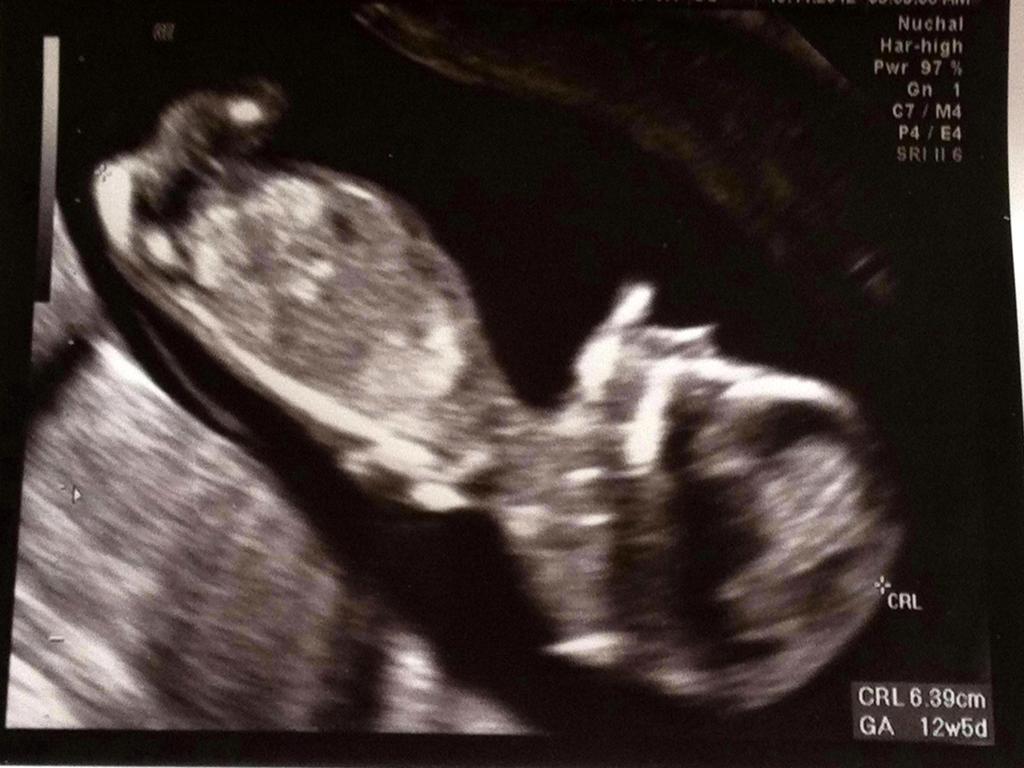

Hi had my NT scan last week.... reports are still awaited... so only have this one pic rt now... will add more photos later... looking forward for your guesses...